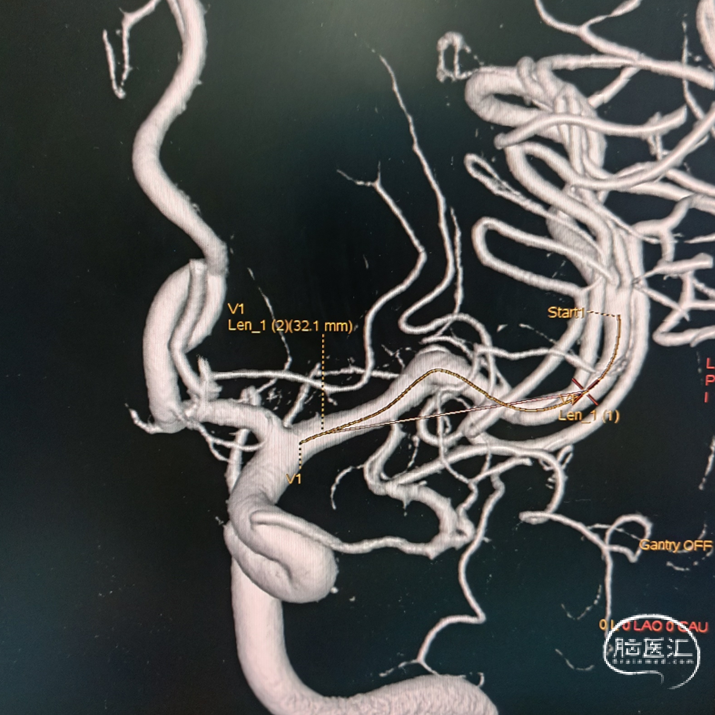

拟选用4.0*20 Pipeline™ Flex血流导向密网支架,远端铆钉在M2段拐弯以远,近端着陆在M1段起始,如图:

术中造影、减影像及3D-DSA可见支架打开充分。微导丝辅助将Phenom™ 27 微导管送至M3段尽可能远的位置,支撑导管送至M1段尽可能接近动脉瘤。